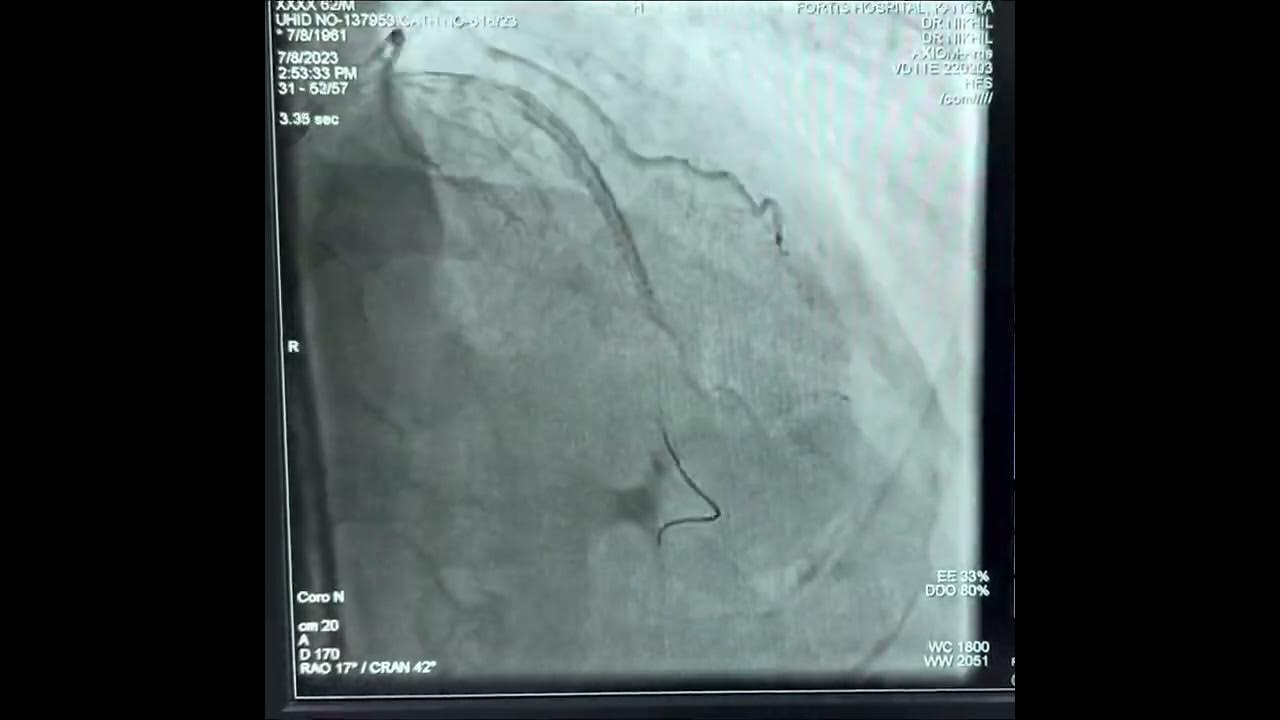

Ping Pong Guide Catheter Technique . we report a novel technique for performing retrograde interventions on a coronary chronic total occlusion through.

we report a novel technique for performing retrograde interventions on a coronary chronic total occlusion through.